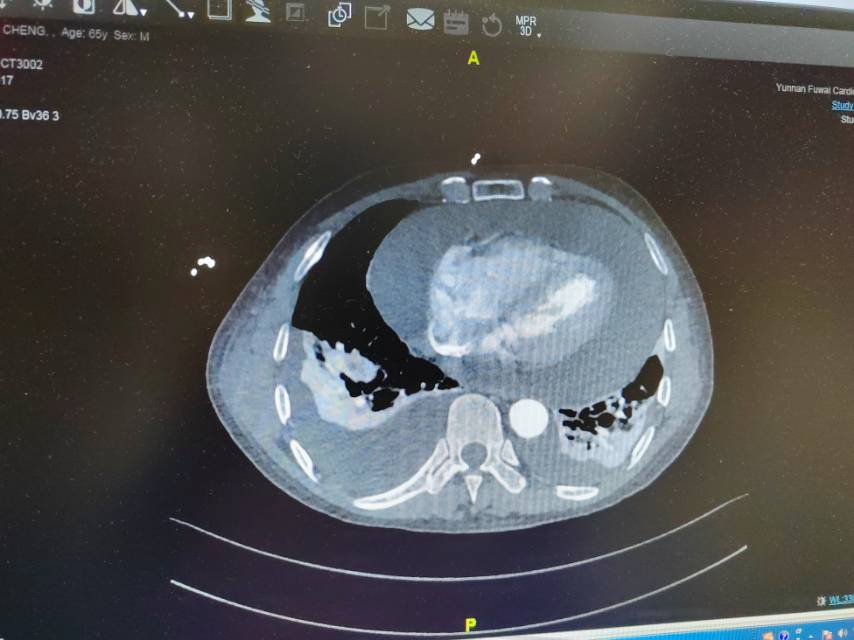

病人至急诊就诊,一旦急诊心脏超声、主动脉CT提示主动脉夹层,并存在血性心包积液,那么,该患者的术前准备紧凑性及进入手术室手术的画面,可能会是“x2.0”甚至更高倍数的播放速度。

主动脉夹层(未切开)

主动脉夹层(切开主动脉)

主动脉夹层撕裂内膜及血管壁,以及假腔内血栓

术后复查CT